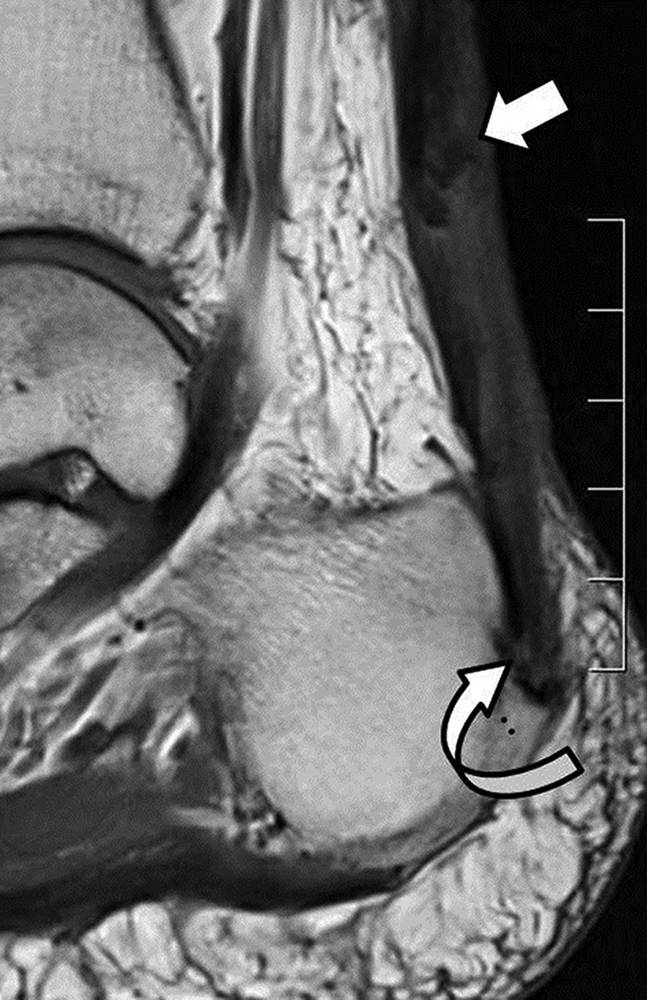

图4A-男,43岁,从马身上掉下来,经历过疼痛,踝关节背部出现瘀伤。A,在损伤后2天获得的X线照片显示了在关节上方约5cm处的跟腱中的骨片(箭头)。

图4B-男,43岁,从马身上掉下来,经历过疼痛,踝关节背部出现瘀伤。B,损伤后6周获得的矢状T1加权MR图像显示加厚的跟腱。 在腱内存在不均匀的信号强度,低信号强度的区域(直箭头)在撕脱位置上方约5cm处, 结节撕脱缺损(弯曲的箭头)